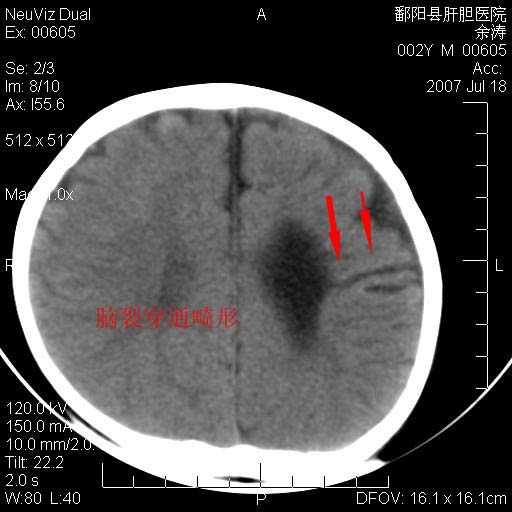

男性 2岁:平时智力障碍。外伤后行颅脑平扫。

1\\脑裂畸形

开唇型脑裂畸形

脑裂畸形  血管畸形

考虑1.脑裂畸形。2.血管畸形。

脑裂畸形  血管畸形 支持

脑裂畸形, 血管畸形.